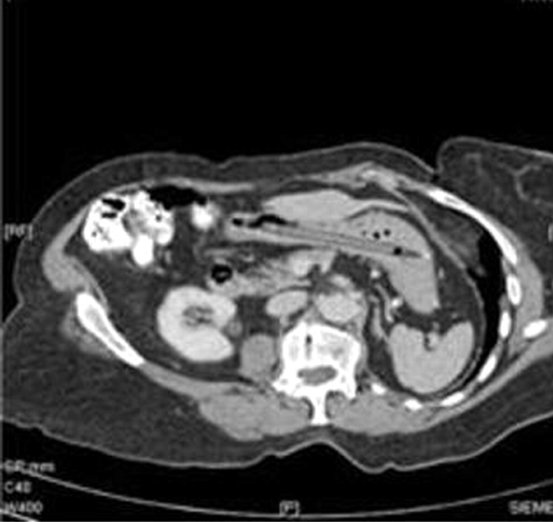

რიყის ქვები

მეგობარ ბიჭზე გაბრაზებულმა ერთმა გოგონამ ჩინეთიდან პროტესტის ნიშნად და ბრაზის გამოსახატად 20-ზე მეტი რიყის ქვა გადაყლაპა. როგორც თავად განაცხადა, ქვები მის საჭმლის მომნელებელ სისტებაში ერთმანეთს "უსიამოვნოდ ეჯახებოდნენ" და ტკივილს იწვევდნენ.